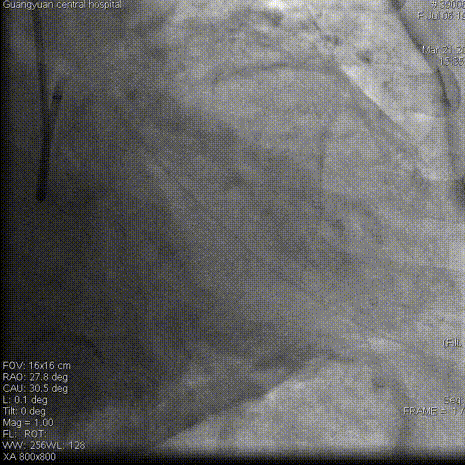

冠脉造影

左冠造影:左冠状动脉主干未见明显狭窄,前降支近中段慢性闭塞;回旋支近中段狭窄90%。

右冠造影:右冠状动脉近中段可见斑块,后降支近段狭窄60%。右冠远端可见向前降支中远段侧枝供血。

双侧造影:前降支近中段闭塞段清晰可见。